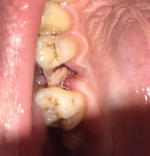

Фото белого налета в лунке после удаления зуба

В крови человека содержатся вещества, которые при нарушении стенок сосудов образуют тромб из фибрина, препятствующий открытию кровотечения. В ротовой полости этому процессу способствуют и особые компоненты слюны. Часть фибрина оседает на поверхности раны. У некоторых людей этот слой практически не заметен, у других образуется видимый фибринозный налет белого цвета, как на месте вырванного зуба на фото справа.

Если зуб раскрошился при захвате щипцами, внутри лунки могут оставаться осколки корня, как на фото справа. Они препятствуют заживлению десны, травмируют окружающие мягкие ткани и могут спровоцировать нагноение. Наиболее часто осколки остаются в лунке после удаления зубов мудрости, что связано с их неровными корнями.